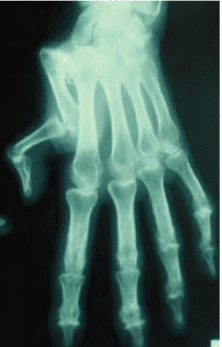

La gravité de la rhizarthrose se mesure en quatre niveaux, déterminés par l’analyse radiographique :

- Au stade 1, l’articulation garde une apparence normale ou s’élargit légèrement.

- Le stade 2 montre un pincement discret de l’articulation, avec la formation d’ostéophytes de moins de 2 mm.

- Le stade 3 se caractérise par une destruction avancée : sclérose osseuse, ostéophytes et fragments articulaires dépassant 2 mm.

- Le stade 4 signe l’atteinte des deux surfaces articulaires, tant trapézo-métacarpiennes que scaphoïdes-trapéziales, où prolifèrent les ostéophytes.